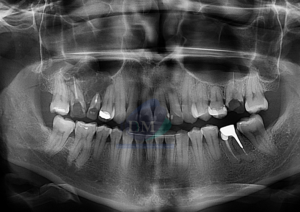

Paciente femenino de 16 años acude al Instituto de Diagnóstico Maxilofacial (sede Miraflores) para evaluación quirúrgica. Radiografia Panorámica A la evaluación de la radiografía panorámica